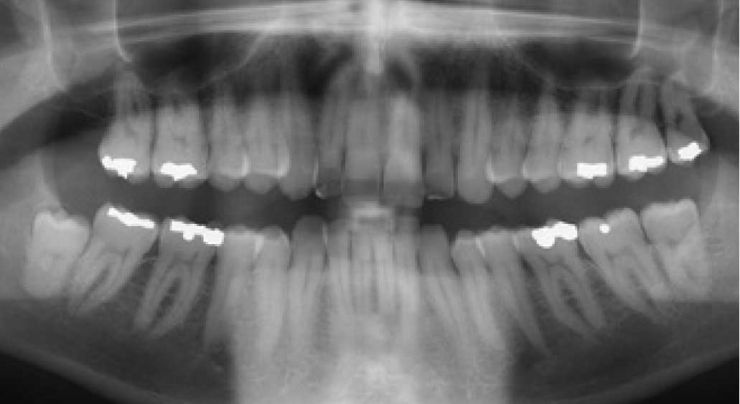

При осмотре ортопантомограмма показала наличие ретинированных третьих моляров. Было принято решение о хирургическом вмешательстве – удалении зубов мудрости. После прохождения лечения отсутствие боли в шее сохраняется уже более 3 лет.